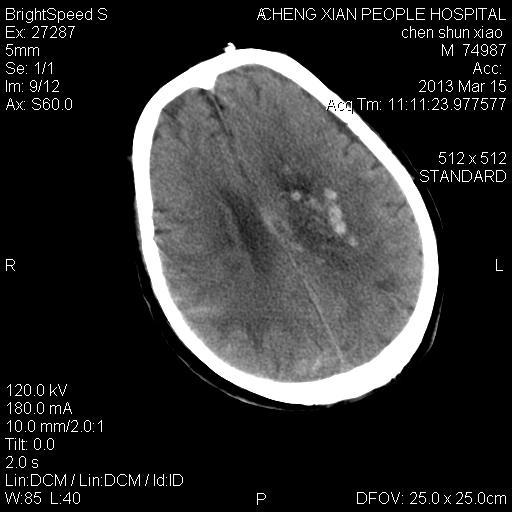

患者陈++,男,71岁。因“昏迷四小时,伴右侧肢体活动受限”以“脑出血”收住院。发病后12小时用“改良立体定向-软通道微创介入新技术治疗脑出血”。术后24小时颅内出血大部被清除,患者神志清晰。右侧肢体肌力0级。

患者陈++,男,71岁。因“昏迷四小时,伴右侧肢体活动受限”以“脑出血”收住院。发病后12小时用“改良立体定向-软通道微创介入新技术治疗脑出血”。术后24小时颅内出血大部被清除,患者神志清晰。右侧肢体肌力0级。